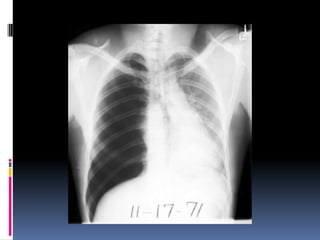

Heart

   Size

   Shape

   Silhouette-margins should be sharp

   Diameter (>1/2 thoracic diameter is

enlarged heart)

 AP views make heart appear larger than it

actually is.

Costo-phrenic / cardiophrenic angles

Margins should

be sharp